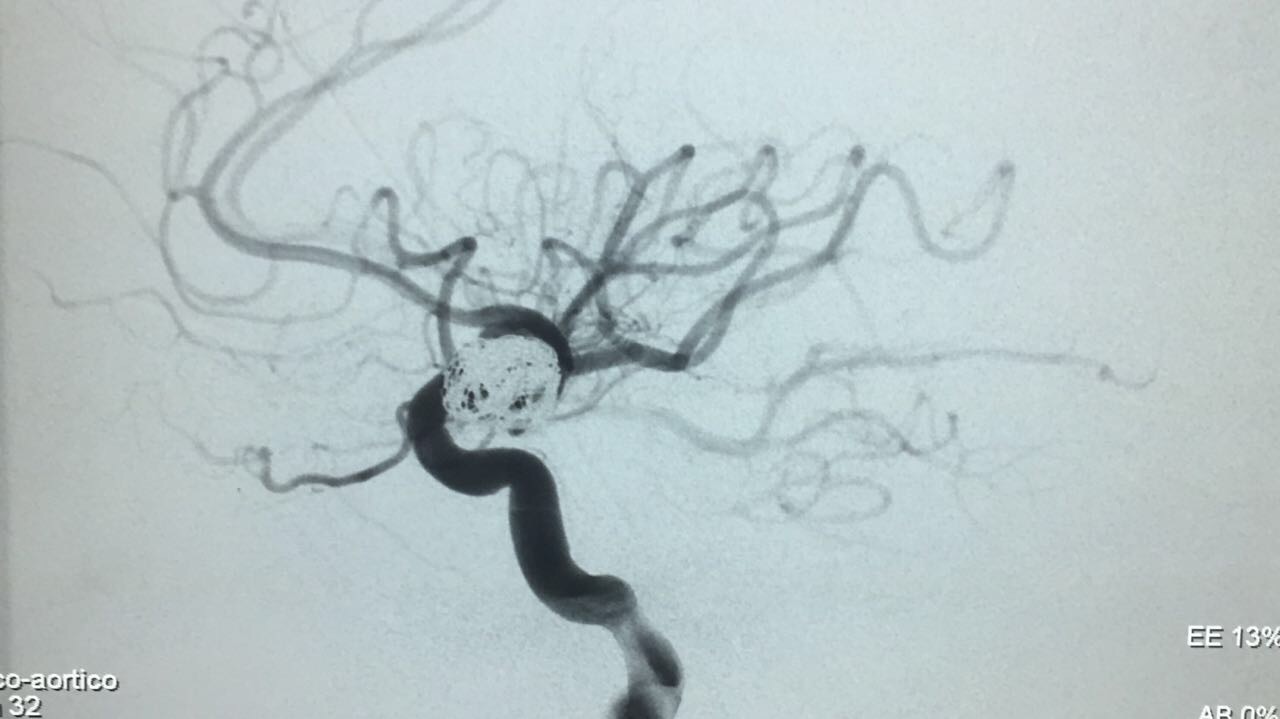

Embolização de Aneurisma segmento Oftálmico

Paciente foi então encaminhada ao setor de hemodinâmica sendo realizado Angiografia cerebral Digital e evidenciado aneurisma de segmento oftálmico da artéria carótida interna esquerda. Realizado embolização do aneurisma com microespirais, sem intercorrências. A paciente permanece em bom estado geral e neurológico recuperando em pós operatório imediato.